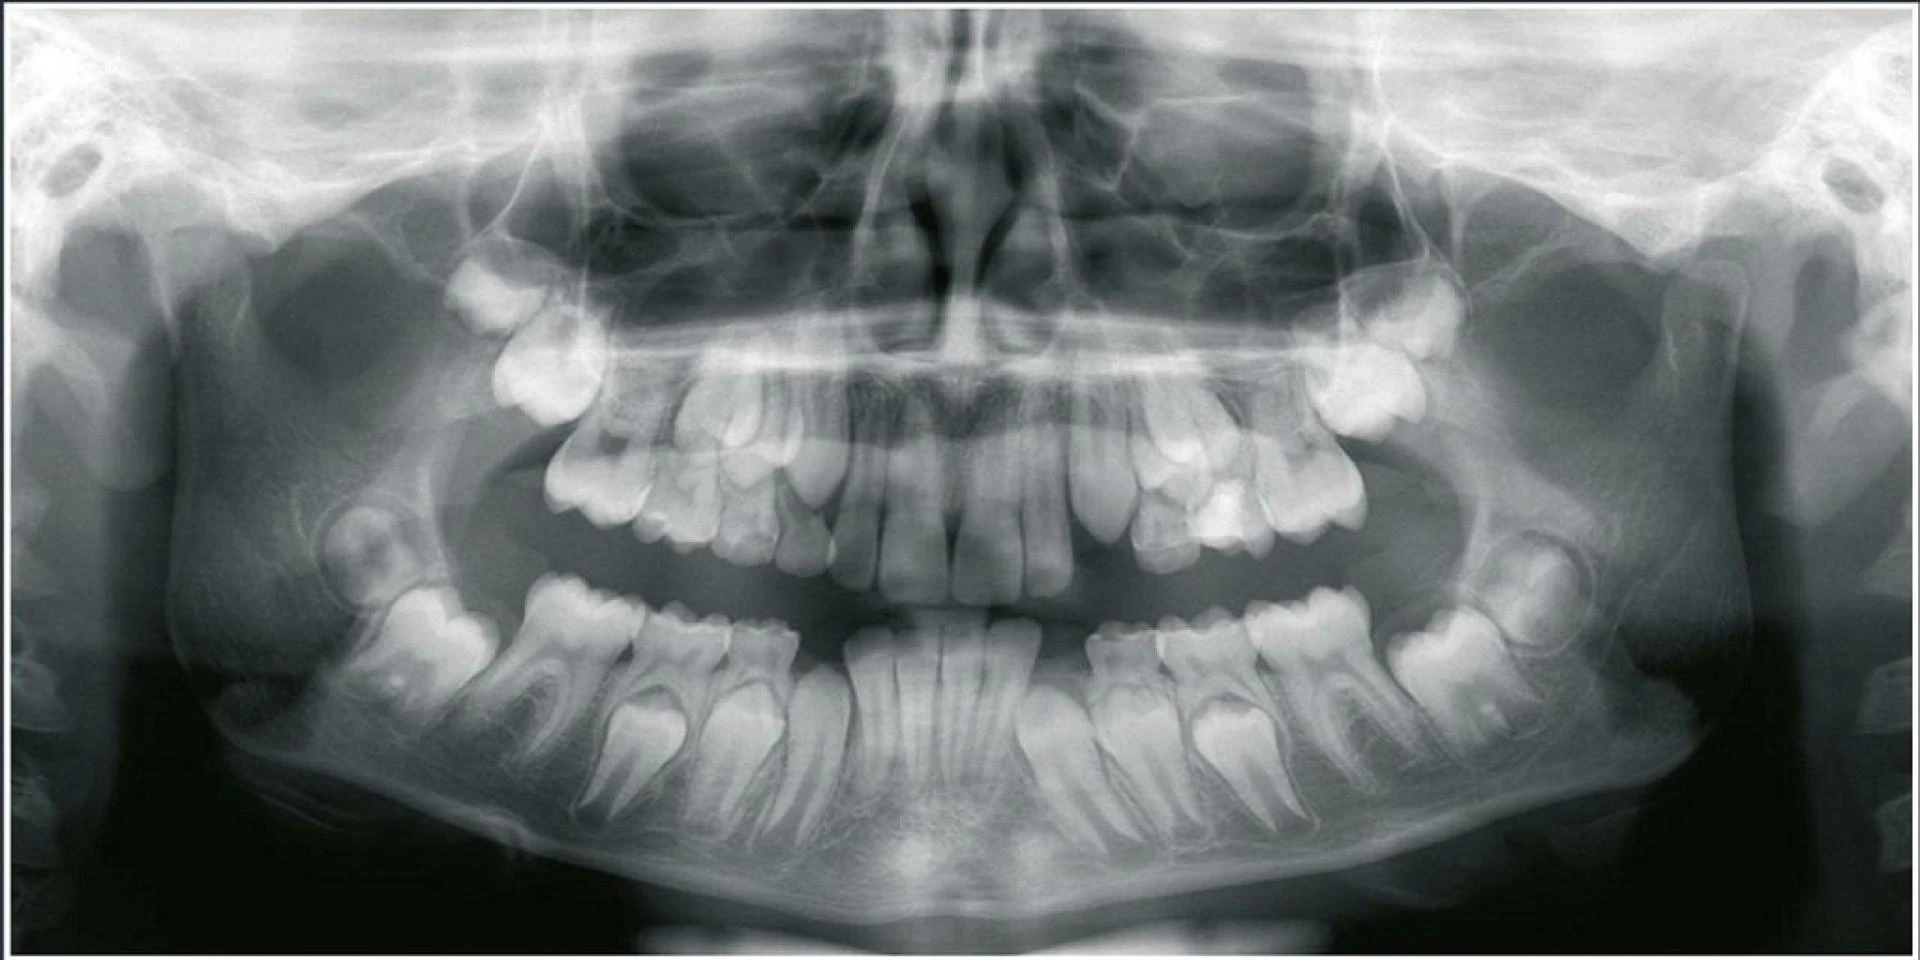

Dental CBCT provides several distinct advantages over 2D panoramic dental X-ray systems. A CBCT scan provides advanced visualization of oral and maxillofacial structures, enabling faster, more accurate diagnoses while helping to minimize the need for re-treatment.

In addition to helping improve diagnosis and treatment planning, dental CBCT also helps enhance patient communication and treatment acceptance. Providing your patients with a three-dimensional view of their anatomy can help them better understand their dental conditions and accept your treatment recommendations.